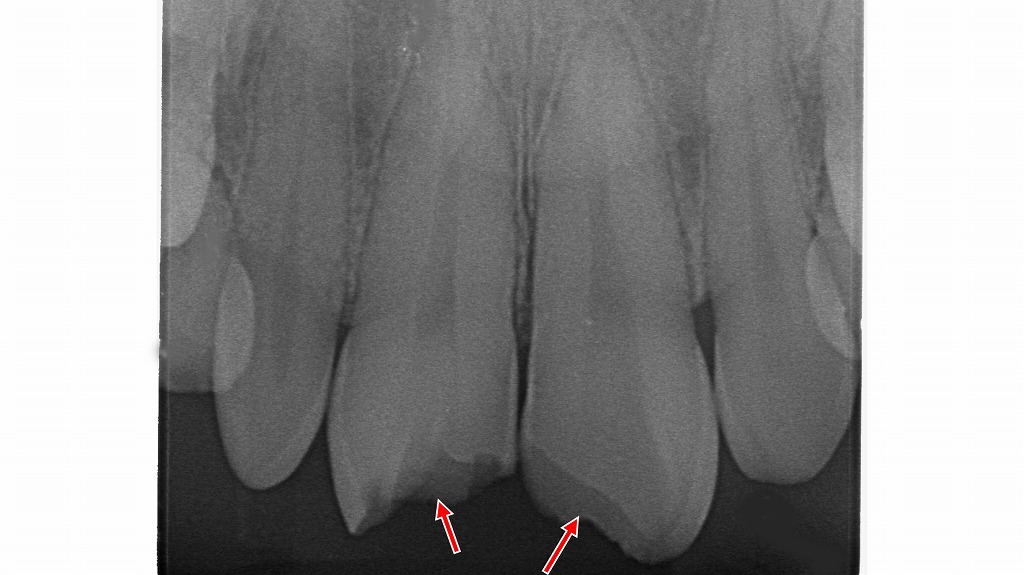

転倒や衝突などの外傷により、前歯の先端が欠けている状態です(矢印部)。歯が折れても痛みが少ない場合がありますが、内部の神経(歯髄)がダメージを受けていることもあり、放置すると変色や感染につながる可能性があります。外傷後は見た目に問題がなくても、早めに歯科での診察・レントゲン検査を受けることが大切です。